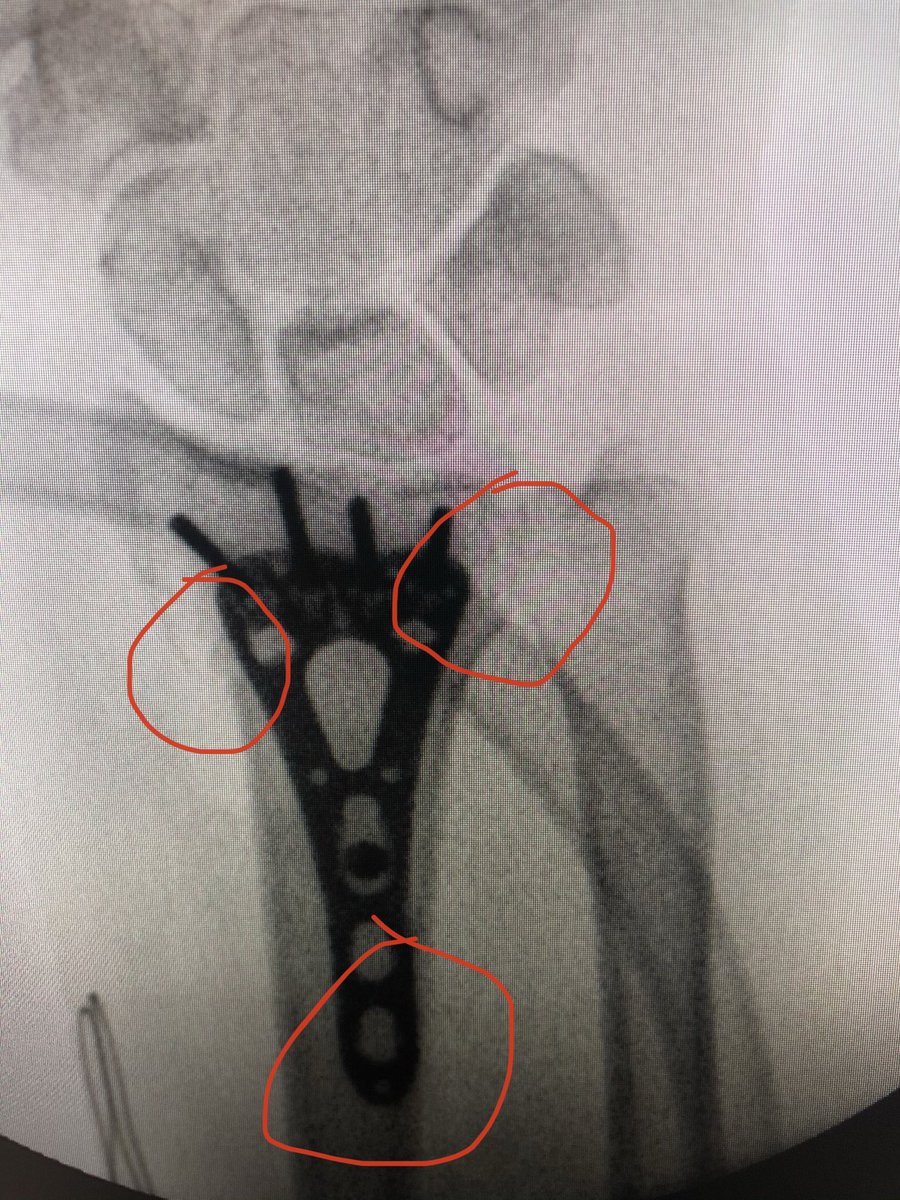

The lamina spreader goes in with the oblong hole cortical screw loosened a couple turns, this corrects alignment, tighten the screw and place more proximal locking screws to โ€˜fixโ€™ the plate position now. Inclination, DRUJ and plate position are corrected.

Check 20 degrees elevated lateral view to see safety of the joint and DRUJ view to make sure no screws violate DRUJ or are too long dorsally.